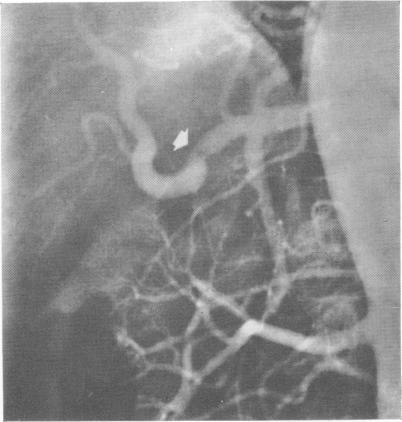

Repair of Hepatic and Superior Mesenteric Artery Injury: Patency Demonstrated by Aortography.

Ann Surg. 1965 Nov;162(5):869-72. doi: 10.1097/00000658-196511000-00008.